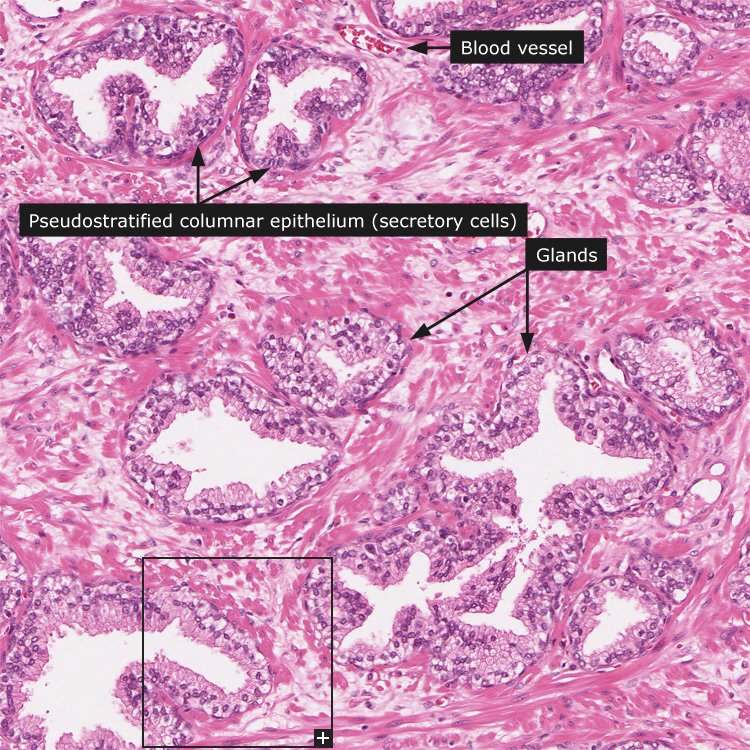

Простата, обычно ассоциируемая с мужским здоровьем после полового созревания, также присутствует у детей, хотя и в значительно меньших размерах. Этот орган, расположенный под мочевым пузырем и окружающий уретру, играет роль в выработке жидкости, которая составляет часть семенной жидкости. Несмотря на то, что проблемы с простатой у детей встречаются редко, понимание её развития и потенциальных патологий важно для ранней диагностики и лечения.